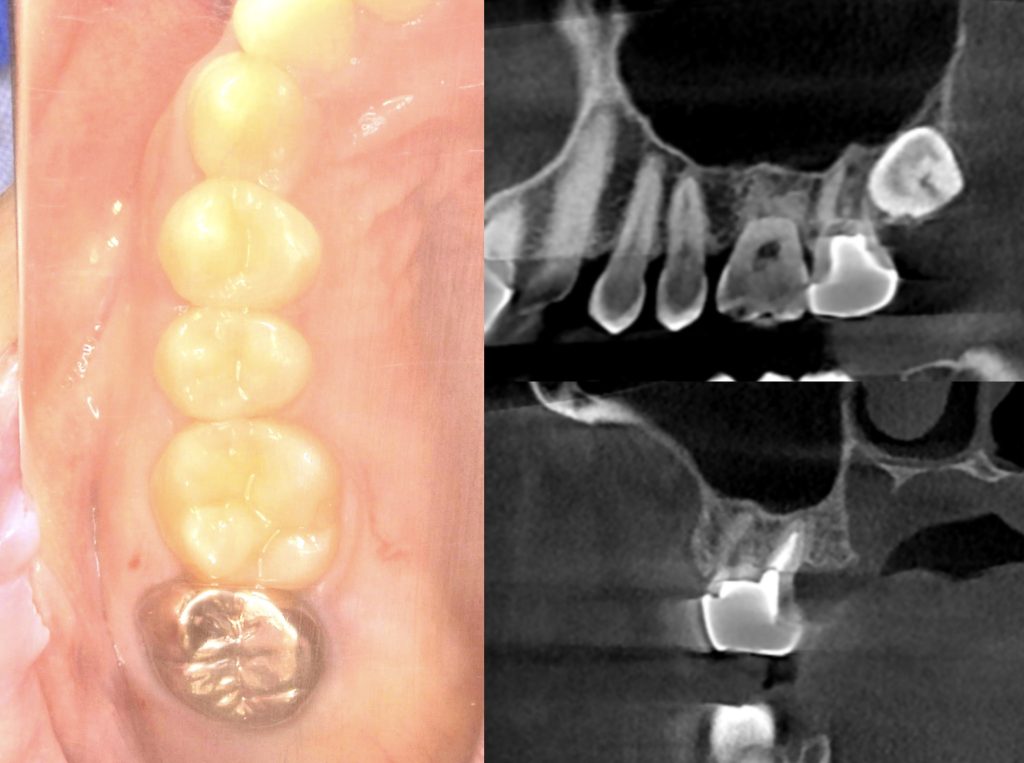

下記の症例は新しくローンチされるインプラントを前もって使用感を確認する為に、適したケースに使わせていただいております。

今回のケースは新しいインプラントを使うことで、骨造成の負担を減らし、清掃性を高める事ができました。